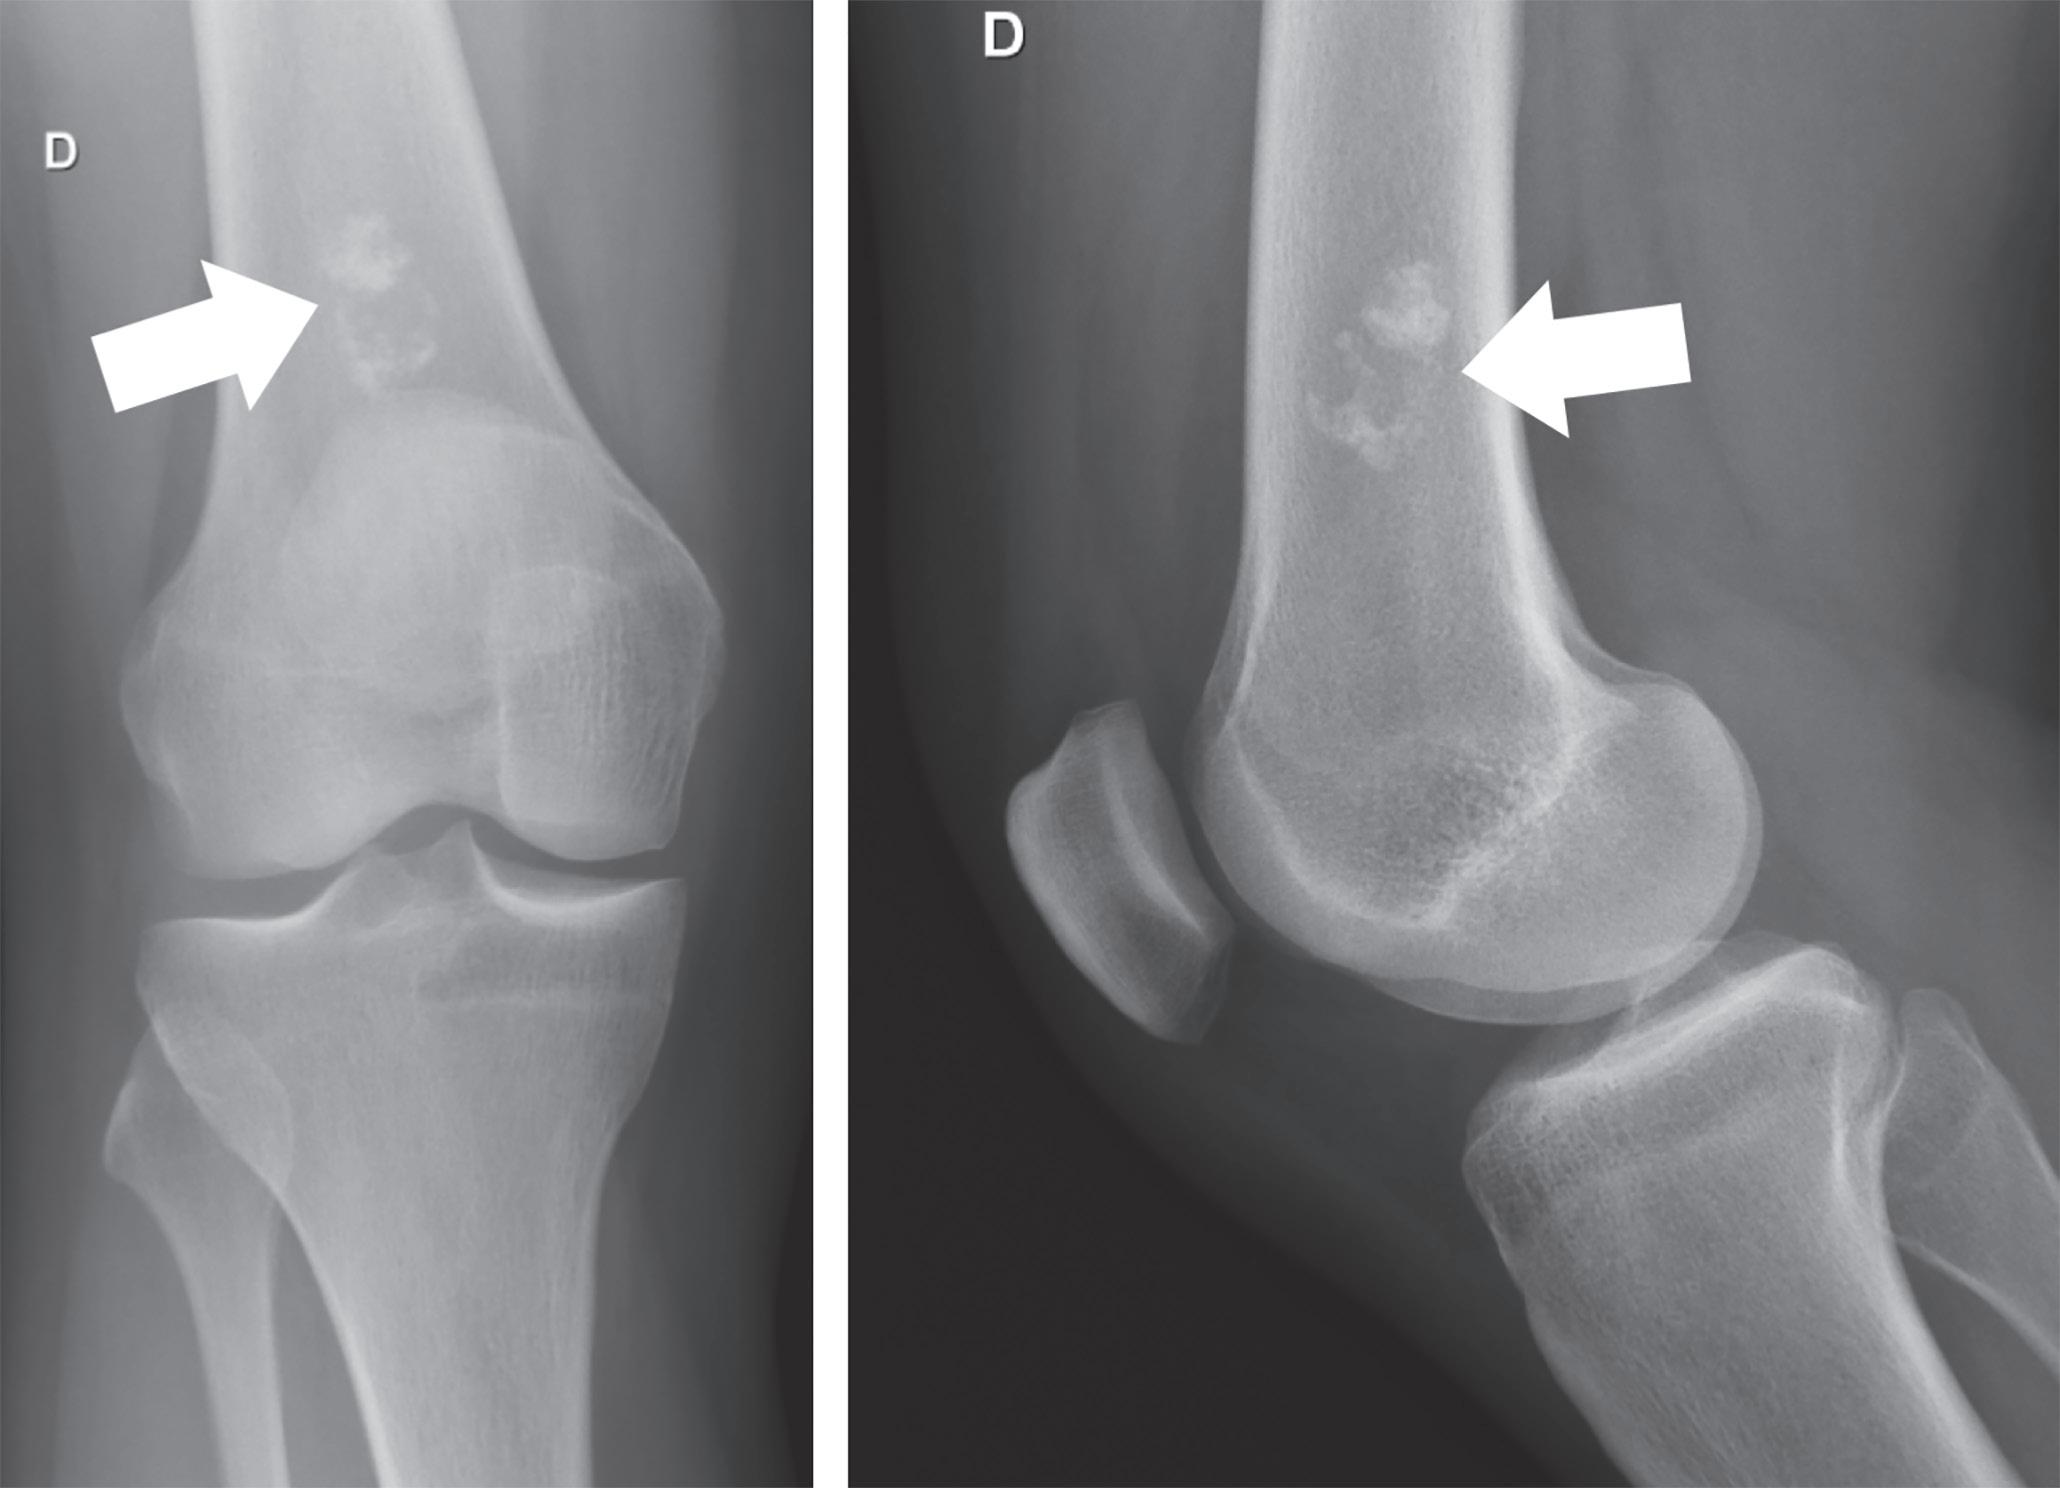

Figura 6.1 – A. Radiografia de fibroma não ossificante da tíbia; B. Radiografia de osteocondroma do fémur; C. Radiografia de quisto ósseo simples do úmero; D. Radiografia de encondroma do fémur. Perante uma imagem radiográfica, são três as questões essenciais a responder: 3.3.1 Onde está a lesão? Existem alguns tumores ósseos que são característicos de certas áreas anatómicas, como é o caso do adamantinoma, que é quase exclusivo da tíbia ou cúbito, ou do encondroma,

O raio-X convencional continua a ser o primeiro exame a realizar perante a suspeita de tumor musculoesquelético. Por vezes, o padrão imagiológico é tão típico que define desde logo o diagnóstico, tal como acontece com fibroma não ossificante (figura 6.1A), osteocon droma (figura 6.1B), quisto ósseo simples (figura 6.1C) e encondroma (figura 6.1D).

A B C D